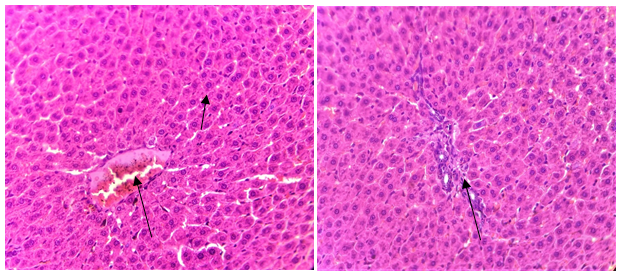

The results of the ethanol-induced hepatotoxicity model are shown in table 1 and 2. Whereas, the results of anti-tubercular drugs-induced (INH+RIF) hepatotoxicity model are represented in table 2 and fig. 1, 2 and 3. Oral administration of hepatotoxic agents like ethanol and INH+RIF showed a remarkable rise in the serum levels of AST, ALT, ALP, GGT, Urea and creatinine (biochemical markers). Whereas pretreatment with Silymarin (100 mg/kg) and MC+PA at various doses of 200 and 400 mg/kg significantly decreased the elevated profile of the serum biochemical markers when compared to positive groups of two models. Anti-oxidant status was measured using liver homogenate in both the models, and there was a significant reduction in SOD activity caused by ethanol and INH+RIF administration when compared with normal, which was enhanced by treating with the combined extract (MC+PA) at both doses and also by silymarin. Further, the hepatic MDA was also elevated significantly in the positive groups of two models. Pre-treatment with MC+PA (200 and 400 mg/kg) and silymarin reduced the elevated concentrations of MDA in comparison with positive groups of two models (table 2). The histopathological results of positive groups of two models revealed mild degenerative changes of perivenular hepatocytes, distorted architecture, centrilobular necrosis and mild inflammatory cell infiltration. Pre-treatment with silymarin and MC+PA of various doses improved the damaged conditions caused due to ethanol and INH+RIF administration (fig. 4 and 5).

Fig. 4: Effect of MC+PA on histopathological changes in Ethanol-induced hepatotoxicity model

Normal:

Positive:

Standard:

Dose I:

Dose II:

Fig. 5: Effect of MC+PA on histopathological changes in Anti-tubercular drugs-induced hepatotoxicity model

The above results were supported by the histopathological changes in liver tissues. The combined extract exhibited a potent hepatoprotective role in a dose-dependent manner by improving the pathological changes caused by ethanol and anti-tubercular drugs. There is a need for further investigations to understand the mechanism of action of the plant extract through which it is exhibiting the hepatoprotective effect. From the above results, it can be concluded that the synergistic effect of the combined extract is may be due to the presence of phytoconstituents like flavonoids, alkaloids, and polyphenols which are highly responsible for exhibiting hepatoprotective and anti-oxidant activities. Hence, this study represents a novel and attractive ideas to prevent the hepatic injury caused due to the consumption of ethanol and the drugs used in anti-tuberculosis treatment.